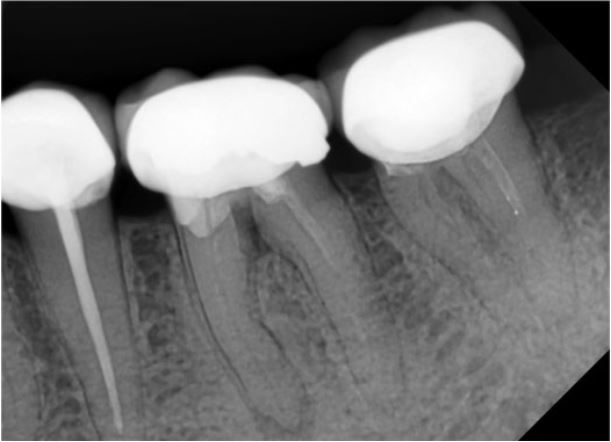

Hình 13.10. Trám bít lại ống tủy bằng gutta-percha và epoxy resin-based sealer (AH Plus®).

Hình 13.11. X quang ngay sau điều trị.